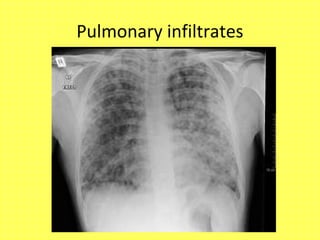

• Pulmonary infiltrates

Pulmonary infiltrates

• Chest X ray / HRCT thorax:

-Pulmonary infiltrates- small vessel vasculitis